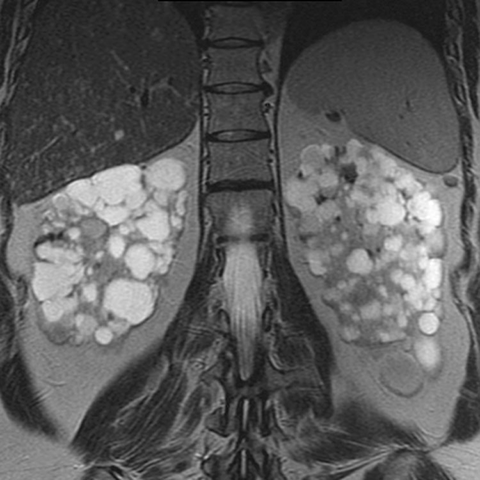

40-year-old woman with progressive renal failure and palpable abdominal masses [2 of 2]